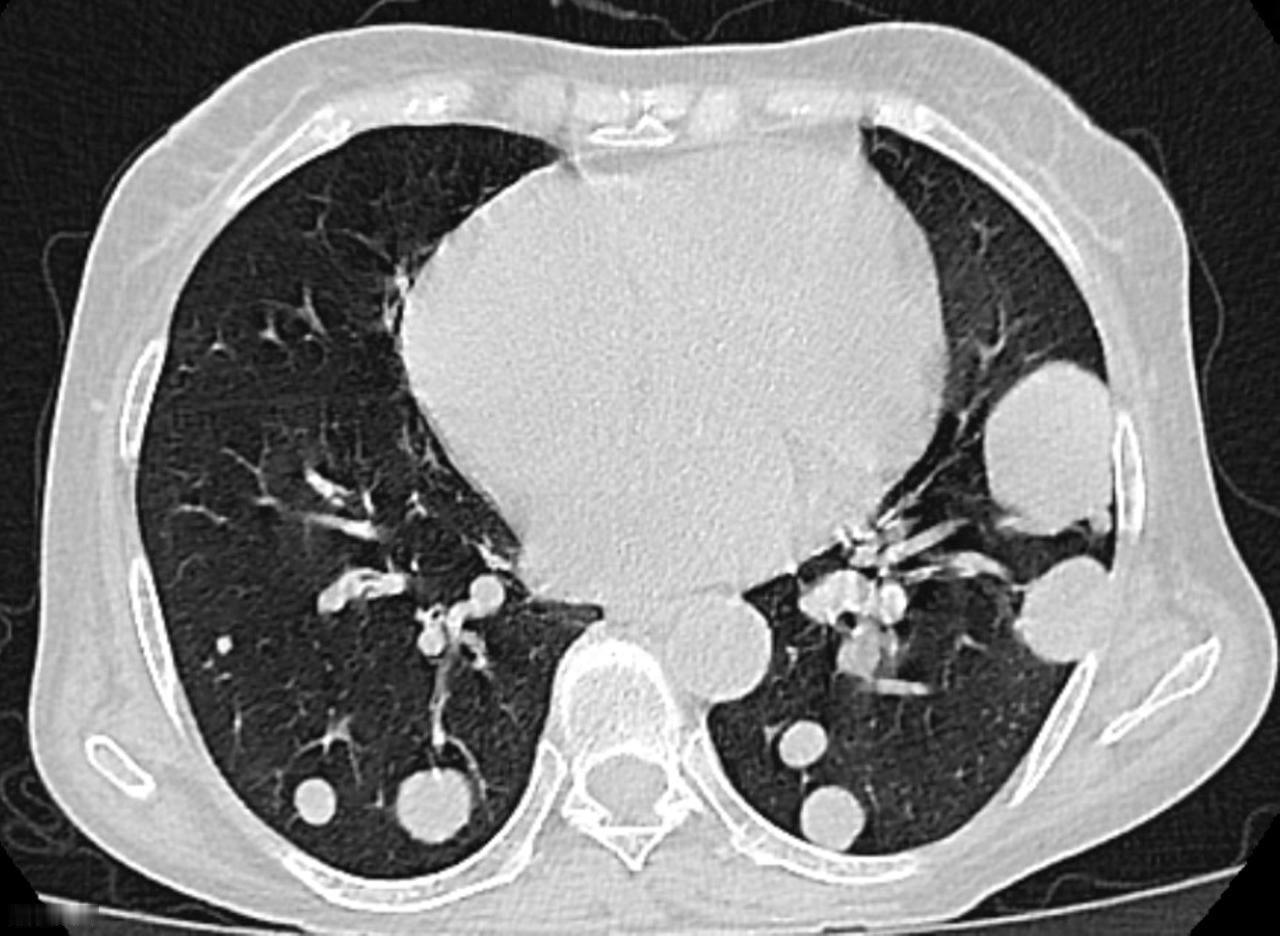

肺结节的克星——川贝母,巧搭这几味,结节慢慢在缩小,赶紧收藏 川贝母化痰软坚、清肺散结,是中医临床不可或缺的一味药,搭配得当,能让顽固的痰结悄悄散开,今天介绍四种经典实用的搭配。 1、川贝母 + 桔梗 作用:软坚化痰、宣肺利咽 表现:胸口像堵着一块石头,说话时间长一点就咽干口干、气不够用,干咳少痰。 辨证:川贝能化痰软坚,把硬结的块儿化开,桔梗能宣肺、把深层的痰往外带出去。 2、麦冬 + 川贝母 作用:滋阴润肺、化痰散结 表现:肺阴不足,像土地干裂后更容易积灰,结块,平时还伴有手脚心热、舌红少苔,口干、易烦躁,夜间咳嗽更明显 辨证:麦冬滋阴润肺,就像给干枯的土壤洒点水,让肺重新湿润起来;川贝化痰散结,把积在里面的痰核慢慢化散。 3、款冬花 + 川贝母 作用:清肺化痰、利咽止咳 表现:痰多、胸闷,尤其感觉咽喉有黏腻感、早晨痰多,胸口沉重、易疲倦,伸舌头一看,舌苔白厚,这多半是湿痰壅肺。 辨证:款冬花能清肺止咳,把“湿痰的火”降下来;川贝母能把痰气带出去,让堵在中间的东西有一个出口。 4、川贝母 + 麦冬 + 桔梗 作用:气阴双调、软坚化痰 表现:既干咳又有痰、既胸口刺痛又夜里咳嗽 辨证:川贝负责软坚化痰,麦冬滋阴润肺,桔梗宣肺通络,三味同用,能把“干、火、痰、堵”同时调理开 以上内容仅做医学科普,实际调理均需结合自身实际情况,辨证加减,不可单独使用。 肺肺结节[超话]中医